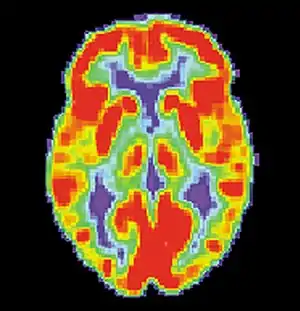

Brain positron emission tomography is a form of positron emission tomography (PET) that is used to measure brain metabolism and the distribution of exogenous radiolabeled chemical agents throughout the brain. PET measures emissions from radioactively labeled metabolically active chemicals that have been injected into the bloodstream. The emission data from brain PET are computer-processed to produce multi-dimensional images of the distribution of the chemicals throughout the brain.[1]:57

The positron emitting radioisotopes used are usually produced by a cyclotron, and chemicals are labeled with these radioactive atoms. The radioisotopes used in clinics are normally 18F (fluoride), 11C (carbon) and 15O (oxygen). The labeled compound, called a radiotracer or radioligand, is injected into the bloodstream and eventually makes its way to the brain through blood circulation. Detectors in the PET scanner detect the radioactivity as the compound charges in various regions of the brain. A computer uses the data gathered by the detectors to create multi-dimensional (normally 3-dimensional volumetric or 4-dimensional time-varying) images that show the distribution of the radiotracer in the brain following the time. Especially useful are a wide array of ligands used to map different aspects of neurotransmitter activity, with by far the most commonly used PET tracer being a labeled form of glucose, such as fluorodeoxyglucose (18F).[2]

The greatest benefit of PET scanning is that different compounds can show flow and oxygen, and glucose metabolism in the tissues of the working brain. These measurements reflect the amount of brain activity in the various regions of the brain and allow to learn more about how the brain works. PET scans were superior to all other metabolic imaging methods in terms of resolution and speed of completion (as little as 30 seconds), when they first became available. The improved resolution permitted better study to be made as to the area of the brain activated by a particular task. The biggest drawback of PET scanning is that because the radioactivity decays rapidly, it is limited to monitoring short tasks.[1]:60>